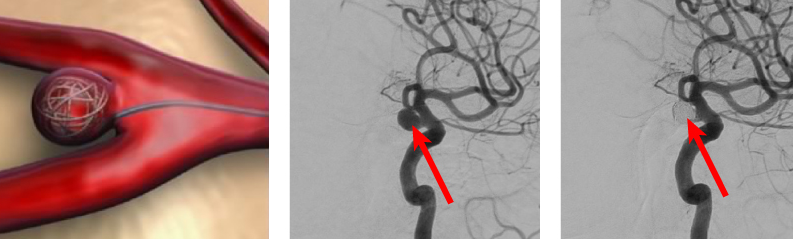

② 코일 색전술: 대퇴부에서 삽입한 카테터를 통해 뇌혈관으로 접근해, 동맥류 내에 백금 코일을 넣어 혈류를 차단하는 비개두술입니다.